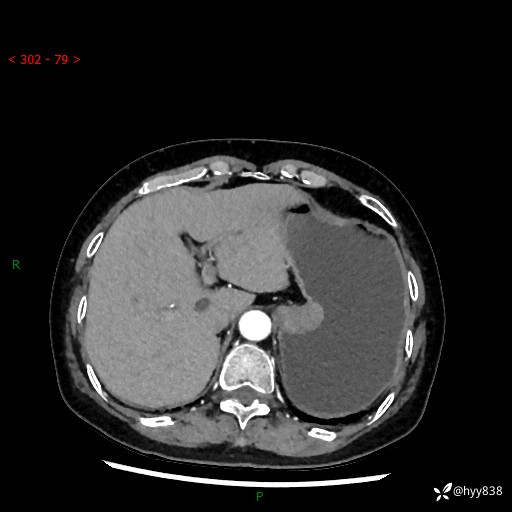

辅助检查:CT

胃CT平扫+增强(动脉期+静脉期)

三期CT值:46hu 58hu 75hu